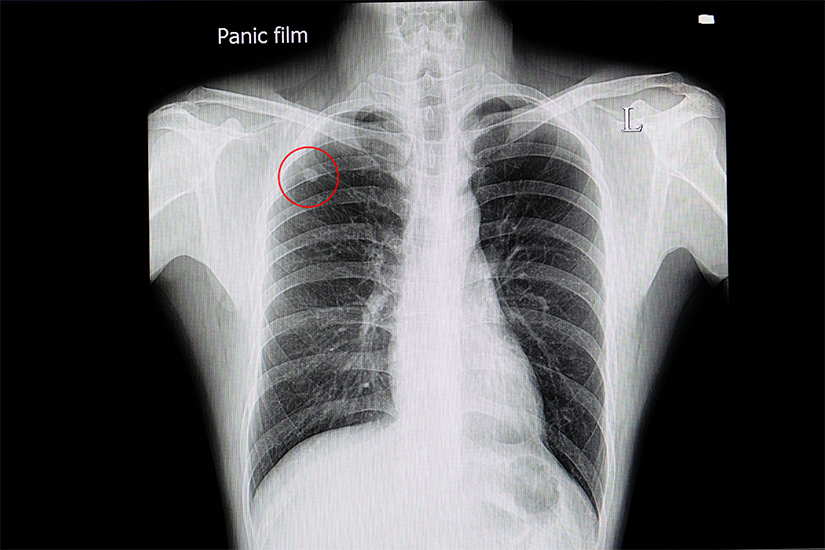

Nodulul pumonar solitar (NPS) este definit ca o leziune unica < 3 cm in diametru, complet inconjurata de tesut pulmonar sanatos, care nu atinge hilul (zona din plamani prin care intra si ies vasele, nervii si bronhiile) sau mediastinul (zona centrala din torace dintre cei doi plamani) si nu are asociata atelectazie (colapsul unui lob sau unui intreg plaman) sau revarsat pleural (acumulare de lichid in cavitatea pleurala din jurul plamanilor)

Majoritatea persoanelor la care se diagnosticheaza un nodul pulmonar solitar nu au simptome. Frecvent, nodulul pulmonar solitar este detectat intamplator, cand se efectueaza o radiografie sau o tomografie computerizata (CT) toracica pentru alte motive. Perntru ca un nodul pulmonar sa poata fi evidentiat pe o radiografie pulmonara trebuie sa creasca cel putin 1 centimetru in diametru. Tomografia computerizata toracica este o metoda imagistica mult mai precisa, care poate identifica noduli de doar 3-4 mm. Se considera ca nodulul pulmonar solitar este una din cele mai frecvente anomalii pulmonare descoperite accidental radiologic (prin radiografii sau prin tomografii computerizate) care necesita evaluare suplimentara. Aproximativ 150.000 de cazuri sunt diagnosticate in fiecare an in Statele Unite.

Radiografia pulmonara

Deoarece frecvent un nodul pulmonar solitar este identificat accidental pentru prima data cu ocazia efectuarii unei radiografii pulmonare, este este important sa se stabileasca daca nodulul este localizat in plaman sau in afara acestuia. Frecvent sunt confundate cu nodulii pulmonari solitari opacitati extrapulmonare de tesuturi moi, cum ar fi mameloanele, nodulii cutanati sau opacitati generate de anomalii osoase. O radiografie toracica efectuata din profil sau o tomografie computerizata toracica vor confirma localizarea nodulului.

Desi rar pot fi identificati pe radiografia pulmonara noduli de 5 mm, frecvent acestia sunt vizualizati cand au atins o dimensiune de 10 mm in diametru.

Pacientii care au o radiografie toracica mai veche trebuie s-o arate medicului pneumolog pentru a fi comparata cu cea actuala. Acest lucru este important, deoarece se poate determina rata de crestere a unui nodul. Timpul de dublare al majoritatii nodulilor pulmonari maligni este de 1-6 luni si orice nodul care creste mai lent sau mai rapid este mai probabil benign. Daca leziunea este nemodificata radiologic de cel putin 2 ani, probabil ca este benigna.

Radiografia toracica furnizeaza informatii cu privire la dimensiune, forma, margini, rata de crestere si modelul de calcificare. Toate aceste caracteristici pot ajuta la determinarea naturii benigne sau maligne a leziunii. Cu toate acestea, niciuna dintre aceste caracteristici nu este in intregime specifica pentru cancerul pulmonar.

Caracteristicile care pot ajuta la stabilirea diagnosticului cu o certitudine rezonabila includ: un model benign de calcificare, o rata de crestere care este mult mai lenta sau mai rapida decat cea caracteristica cancerului pulmonar, o forma sau un aspect in concordanta cu cel al unei leziuni benigne si dovezi clare ale unei alte boli benigne.